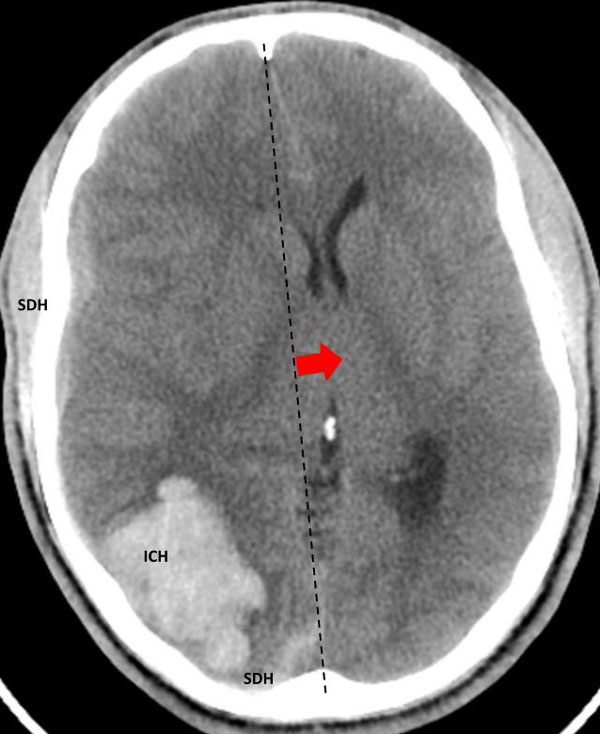

The patient was taken to the angio-suite where an angiogram confirmed a high flow, high pressure AVM fed primarily by the posterior cerebral artery with a small collateral from the middle cerebral artery (Fig 2 and 3). The AVM drained into a tortuous, partially occluded and stenotic single draining vein.

Fig 2. AP view, mid-arterial phase of a right internal carotid artery (ICA) injection. The large tortuous draining vein (yellow star) with the suggestion of clot (dotted circle) can be seen. AVM nidus (red arrow), MCA (middle cerebral artery, ACA (anterior cerebral artery).

Fig 3. Lateral view, late-arterial phase of a right internal carotid artery (ICA) injection. Filling of the AMV (red arrow) by the fetal posterior cerebral artery (PCA) and small middle cerebral artery feeder (blue arrow). The large tortuous draining vein (yellow star) with venous stenosis and the suggestion of clot (dotted circle) can be seen.